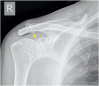

The rotator cuff is a group of four muscles and tendons surrounding the shoulder joint providing it strength and stability. The rotator cuff consists of the subscapularis, supraspinatus, infraspinatus and teres minor. Many shoulder complaints are caused by rotator cuff pathology such as impingement syndrome, tendon tears and other diseases e.g. calcific tendonitis. Diagnosis starts with clinical history and physical examination, after which imaging is often used to help confirm clinical findings depending on the differential diagnosis. The aim of the article is to review the frequently used imaging modalities to assess the rotator cuff and cuff-related disease, specifically focusing on radiography, ultrasonography and magnetic resonance imaging. This article will outline the advantages and disadvantages for each modality and illustrate typical radiological findings of common rotator cuff pathologies.